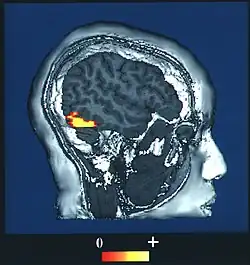

De uitdaging binnen de cognitieve neurowetenschap is de neurale correlaten van bewustzijn te verklaren als een oorzakelijk verband.

De cognitieve neurowetenschap is erin geslaagd toetsbare verklaringsmodellen op te stellen van de 'neurale correlaten van bewustzijn': het wetenschappelijk aantoonbare verband tussen neurologische activiteit in de hersenen en het bewustzijn.[4]